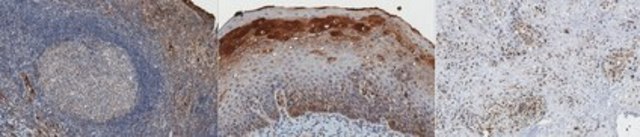

Immunohistochemistry Analysis: A 1:50 dilution from a representative lot detected CtIP in normal human tonsil and human pancreatic cancer tissue.

Clone 11-1 specifically detects CtBP-interacting protein in human tonsils and pancreas.

Evaluated by Immunohistochemistry in human tonsil tissue.

Immunohistochemistry Analysis: A 1:50 dilution of this antibody detected CtIP in human tonsil tissue.